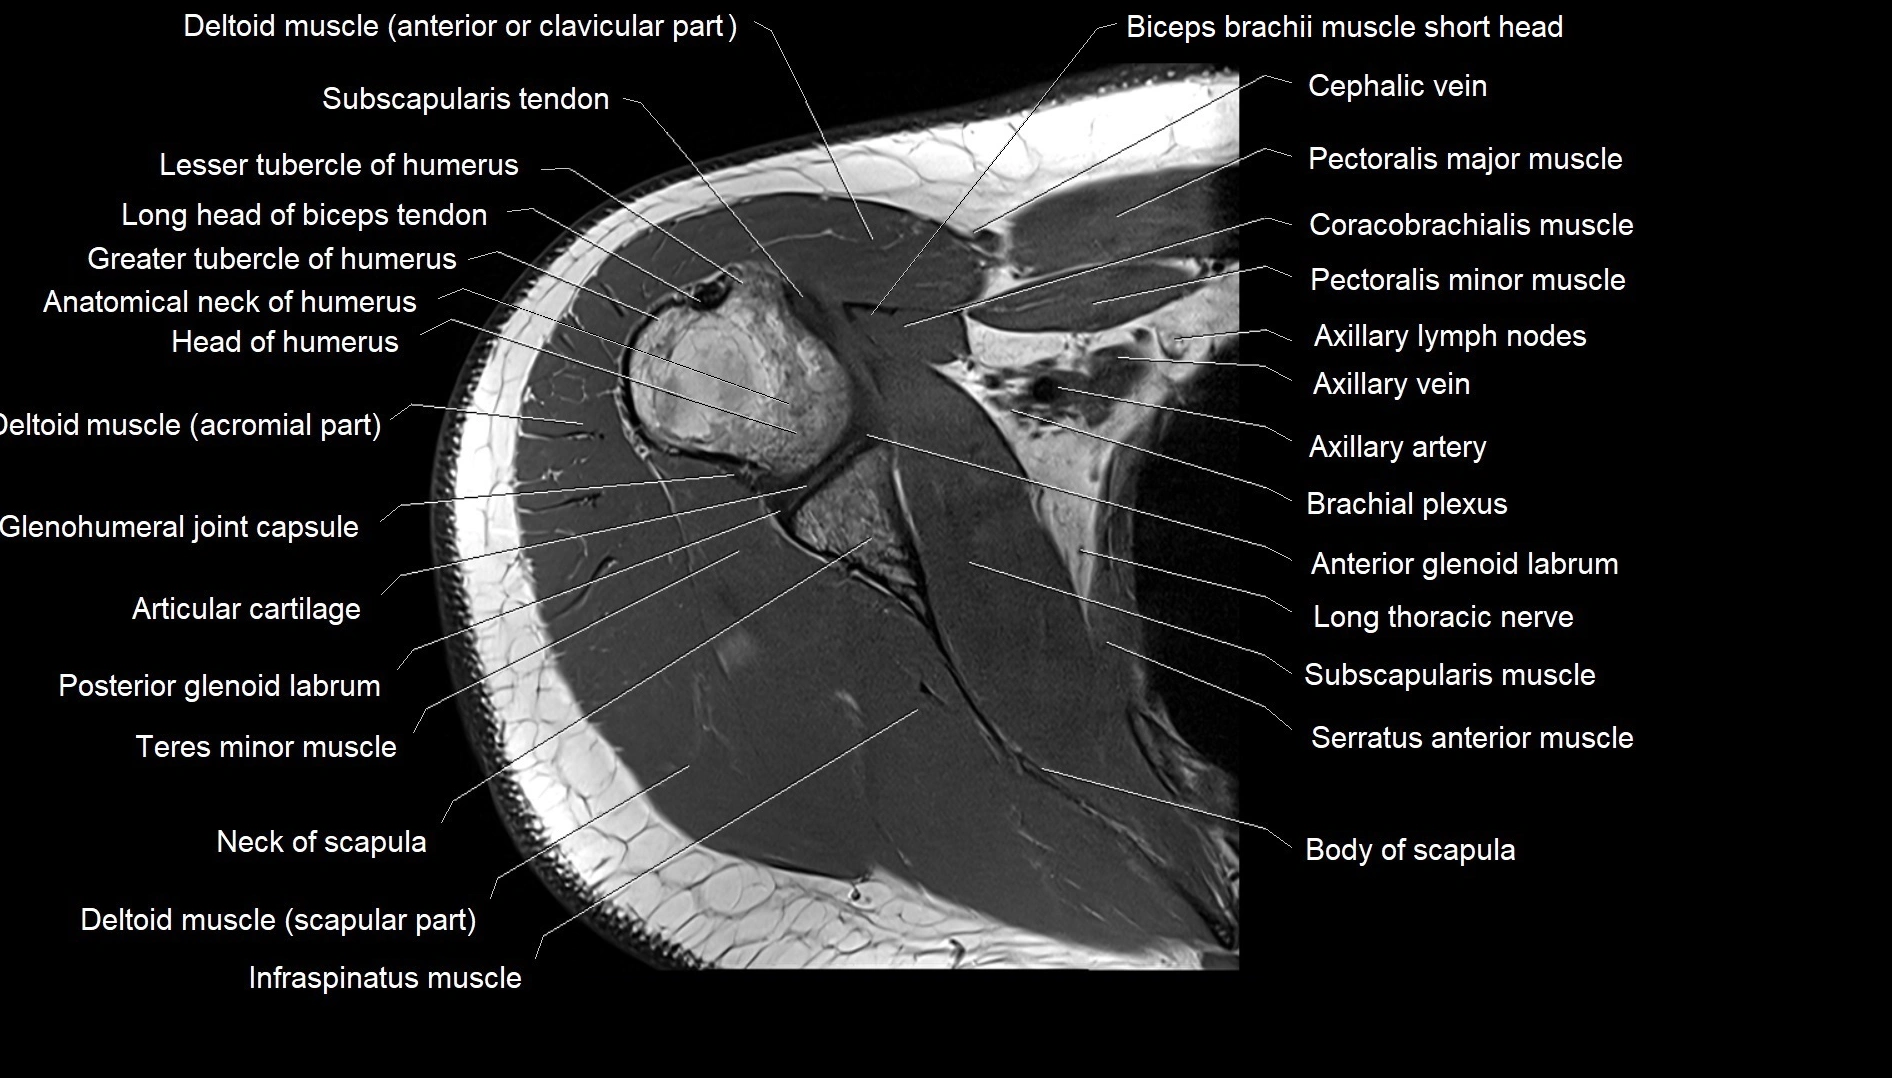

CT image

image